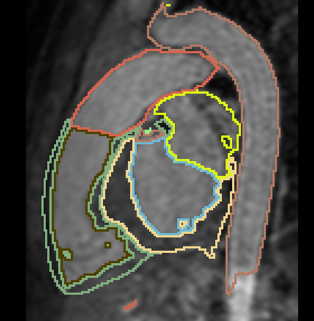

Interactive Deep Learning for Congenital Heart Disease Segmentation

- Aim: segment all cardiac chambers and great vessels from cardiac MRI, for children with congenital heart disease.

- 20 training cases + large anatomical variability - remains a challenge for automatic segmentation.

- Approach: Integrate some interaction from the user, e.g. scribbles or landmarks.

- Already have framework for interactive segmentation. Currently testing using scribbles for aorta segmentation.